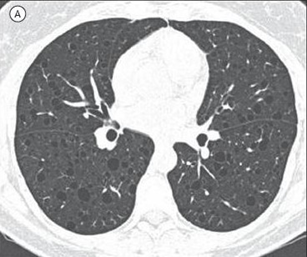

As imagens abaixo estão relacionadas a outras doenças pulmonares císticas.